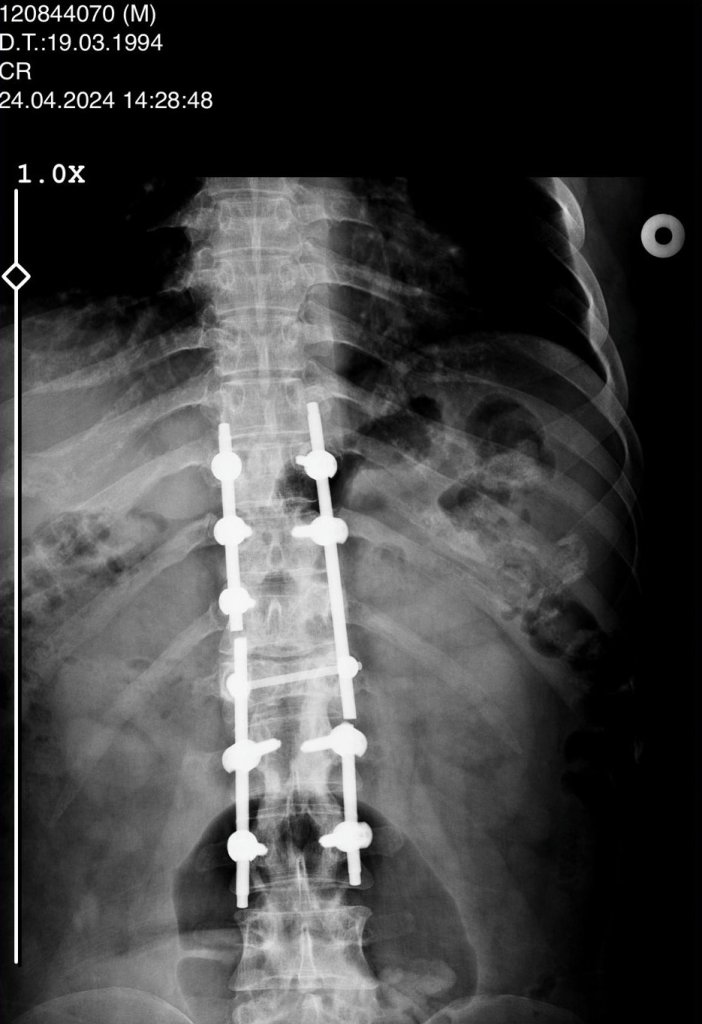

Araçtan çıkarıldıktan sonra Selçuk Üniversitesi Tıp Fakültesi Hastanesi'ne kaldırılan Keşto'nın omurgasının kırıldığı, omuriliğinin zedelendiği belirlendi. Geçirdiği ameliyatın ardından 3 gün yoğun bakımda kalan Keşto, 6 aylık tedaviden sonra taburcu edildi. Bir daha yürüyemeyeceğini öğrenen Keşto, Adana'daki ailesinin evine döndü.